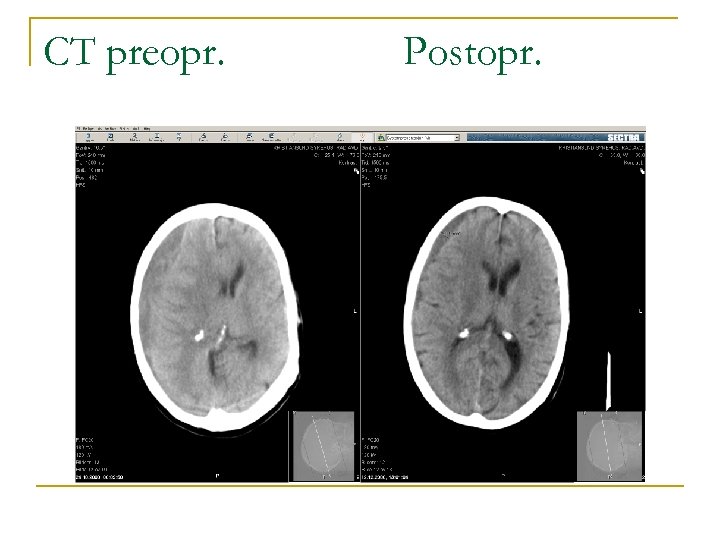

CT preopr. Postopr.

Herr S. , forts. n n n Operert. Hematomet tømte seg med lavt trykk. Utskrevet til hjemmet 1. postoperative dag. Ved kontroll klinisk symptomfri. CT viste 15 mm brem av resthematom. Ved siste kontakt hos fastlegen februar 2011 var han mentalt helt klar, selvhjulpen og tilfredsstilte alle helsekrav til førerkort. Pasienten bor hjemme og steller sin skrøpelige kone.